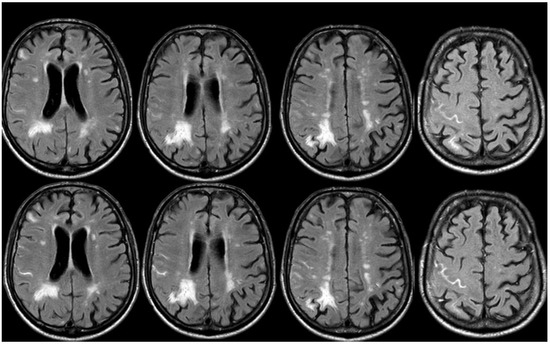

3. May 2014: CAA-Related Inflammation

5. February 2017: First Recurrent CAA-Related Inflammation

7. April 2018: Second Recurrent CAA-Related Inflammation

8. April 2018: Third Recurrent CAA-Related Inflammation